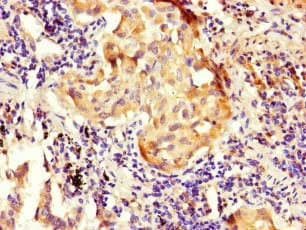

Rabbit Polyclonal NOXA1 antibody. Suitable for WB, IHC-P, ICC/IF and reacts with Mouse, Human samples. Immunogen corresponding to Recombinant Fragment Protein within Human NADPH oxidase activator 1 aa 150-350.

Applications ICC/IF, IHC-P, WB